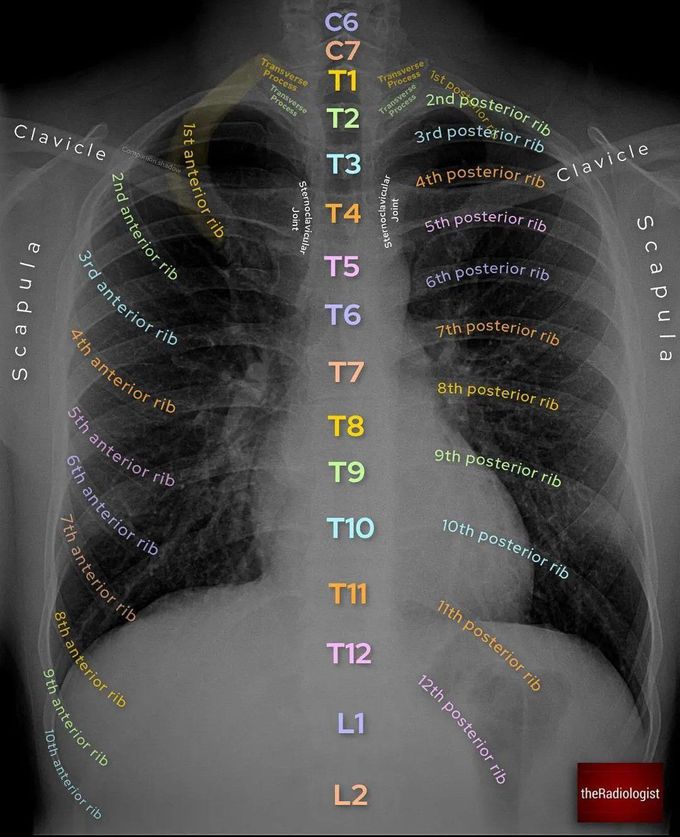

Radiology: Normal Chest X-Rays – Glass Box

glassboxmedicine.comrays radiology cxr coloration

glassboxmedicine.comrays radiology cxr coloration